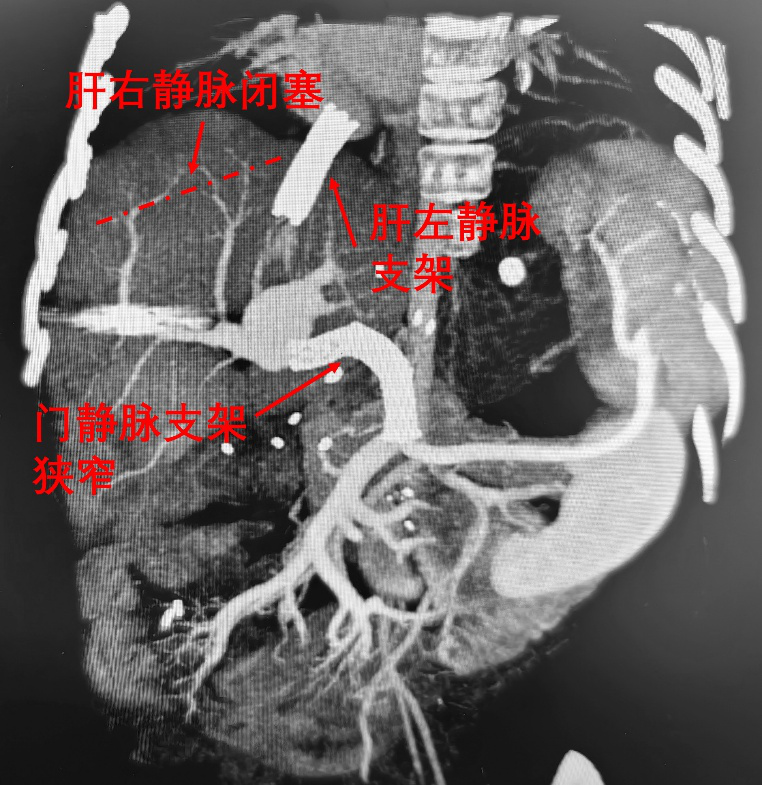

儿童TIPS手术本身难度极高,目前全球18岁以下儿童相关病例报道仅不足200例,国内相关报道更少,而本例患儿的手术难度更是远超常规。其一,常规TIPS手术是经下腔静脉及肝右静脉向腹侧穿刺门静脉,而该患儿下腔静脉及肝右静脉均已闭塞,常规入路完全无法使用,只能从肝左静脉支架内向背侧穿刺门静脉;其二,患儿门静脉内已有两个支架,且支架重度狭窄、开口方向朝下,术中需要精准选择穿刺部位,将TIPS分流道延伸至门静脉支架内,并同期开通狭窄的门静脉支架。可以说,手术团队需要在患儿体内已有的门静脉支架与肝静脉支架之间搭建一条“生命通道”,实现“一桥飞架南北”,从而有效降低门静脉压力、缓解腹水。

图2.患儿术前CT。肝右静脉闭塞,肝后性门静脉高压。门静脉支架重度狭窄,肝前性门静脉高压。两项门静脉高压同时存在,导致肠系膜上静脉回流肝脏受阻,肠表面渗出大量腹腔积液。